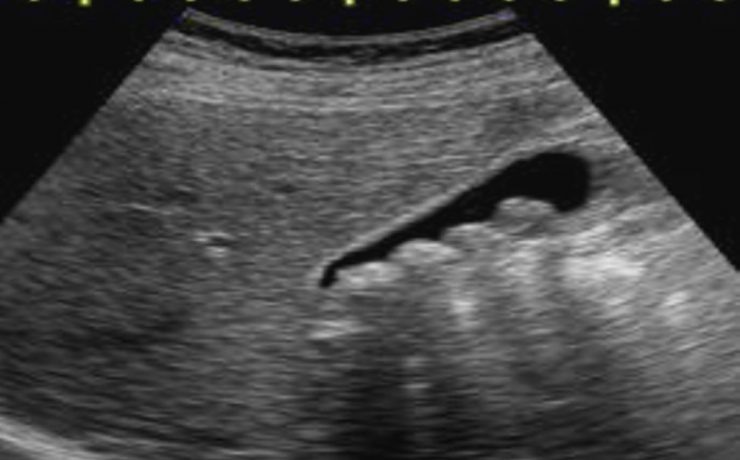

Aspectos ultrasonograficos del riñón

Los riñones órgano parque se encuentra en ambos lado de la columna vertebral dorso-lumbar, se sobreponen parcialmente en la parrilla costal baja y se sitúan retroperitoneales entra la 3ra y 6ta vertebra lumbares. Se dividen para su estudio en corteza, medula y seno; La densidad de su parénquima (medula y